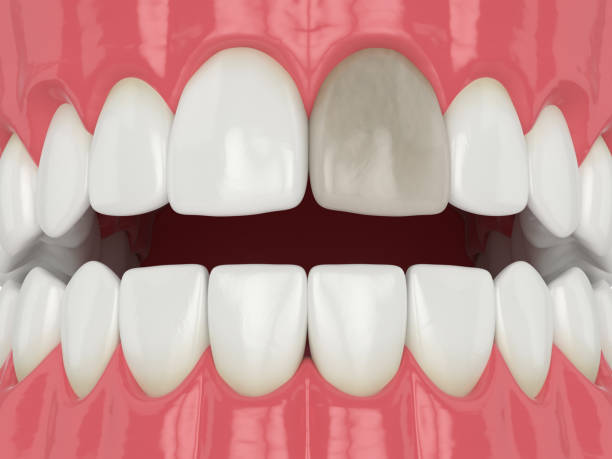

شاید فکر کنید که بعد از عصبکشی، دندان دیگر مرده است و نباید عفونت کند. اما اینطور نیست! ریشه اصلی آبسه، معمولاً باقیماندن باکتریها در کانالهای ریشه یا نشت مجدد آنها به داخل دندان است. این باکتریهای سمج، میتوانند در شکافهای میکروسکوپی، کانالهای فرعی یا حتی بخشهایی که در حین درمان به خوبی پاکسازی نشدهاند، پنهان شوند. با گذشت زمان، این موجودات ریز شروع به تکثیر میکنند و سیستم ایمنی بدن شما هم برای مقابله با آنها وارد عمل میشود. نتیجه این نبرد، تجمع چرک و التهاب است که همان آبسه معروف خودمان میشود. چیزی که از بیرون شاید یک ورم کوچک به نظر برسد، از داخل یک داستان بزرگ عفونی است.

بسیاری از ما تجربه عصبکشی را داریم، یا حداقل کسی را میشناسیم که این درمان را انجام داده است. اما آیا میدانید پشت این واژه ساده، چقدر ظرافت و دقت نهفته است؟ درمان ریشه یا اندودانتیکس، فرآیندی پیچیده برای نجات دندانی است که مغز آن (پالپ) دچار عفونت یا التهاب برگشتناپذیر شده. هدف اصلی این درمان، پاکسازی کامل سیستم کانال ریشه از باکتریها و بافتهای عفونی، شکلدهی و سپس پر کردن آن با مواد زیستسازگار است تا از ورود مجدد باکتریها جلوگیری شود. ساده به نظر میرسد، نه؟ اما در واقعیت، کانالهای ریشه مثل هزارتویی هستند با انشعابات و زوایای پنهان که دسترسی به تمام آنها واقعاً یک چالش بزرگ است.

بزرگترین چالش در درمان ریشه، همین دسترسی و پاکسازی کامل است. دندانپزشک باید مطمئن شود که هیچ باکتری یا بافت عفونی کوچکی در هیچ گوشه و کناری باقی نمانده باشد. کوچکترین غفلت میتواند منجر به آبسه بعد عصب کشی شود. تصور کنید یک سیستم پیچیده را که باید بدون دید مستقیم و فقط با تکیه بر حس و ابزارهای بسیار ظریف، کاملاً تمیز کنید. اینجاست که اهمیت ابزارهای پیشرفته و دقیق به چشم میآید. کانالهای دندان ممکن است بسیار باریک، خمیده یا حتی در بعضی موارد، کلسیفیه (سختشده) باشند که این موضوع کار را برای ابزارهای سنتی بسیار دشوار میکند.